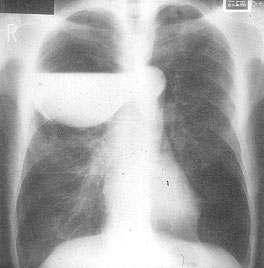

The preoperative work-up should always include clinical and functional evaluation (arterial blood gas analysis and pulmonary function tests with plethysmography), chest x-ray (Figure 6), computed tomography (Figure 7), and V/Q scan (Figure 8). Pulmonary angiography (Figure 9) has been reported to show some advantages in evaluating the underlying lung; however, it is not routinely performed.